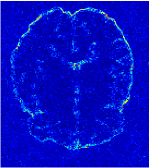

All the experiments are implemented on a Windows workstation with Intel Core i9 CPU at 3.3GHz and an Nvidia GTX-1080Ti GPU with 11GB of graphics card memory via TensorFlow Abadi et al. (2016). The parameters in the proposed network are initialized by using Xavier initialization Glorot and Bengio (2010). We trained the meta-learning network with four tasks synergistically associated with four different CS ratios: 10%, 20%, 30%, and 40%, and test the well-trained model on the testing dataset with the same masks of these four ratios. We have 300 training data for each CS ratio, which amount to total of 1200 images in the training dataset. The results for and MR reconstructions are shown in Tables 5.4 and 5.4 respectively. The associated reconstructed images are displayed in Figures 1 and 3. We also test the well-trained meta-learning model on unseen tasks with radio masks for skewed ratios: 15%, 25%, 35%, and random Cartesian masks with ratios 10%, 20%, 30% and 40%. The task-specific parameter for the unseen tasks are retrained for different masks with different sampling ratios individually with fixed task-invariant parameters . In this experiments, we only need to learn for three skewed CS ratios with radio mask and four regular CS ratios with Cartesian masks. The experimental training proceed on less data and iterations, where we performed on 100 MR images with 50 epochs. For example, for reconstructing MR images with CS ratio 15% radio mask, we fix the parameter and retrain the task-specific parameter on 100 raw data with 50 epochs, then test with renewed on our testing data set with raw measurement that sampled from radio mask with CS ratio 15%. The results associated with radio masks are shown in Table 5.4 and 5.4, Figure 2 and 4 for and images respectively. The results associated with Cartesian masks are list in Table 5.4 and reconstructed images are displayed in Figure 5.

In this section, we test the generalizability of the proposed model that tests on unseen tasks. We fix the well-trained task-invariant parameter and only train for sampling ratios 15%, 25% and 35% with radio masks and sampling ratios 10%, 20%, 30% and 40% with Cartesian masks. In this experiment, we only used 100 training data for each CS ratio and apply a total of 50 epochs. The averaged evaluation values and standard deviations are listed in Table 5.4 and 5.4 for reconstructed T1 and T2 brain images respectively that proceed with radio masks, and Table 5.4 shows the qualitative performance for reconstructed T2 brain image that applied random Cartesian sampling masks. In T1 image reconstruction results, meta-learning improved 1.6921 dB in PSNR for 15% CS ratio, 1.6608 dB for 25% CS ratio, and 0.5764 dB for 35% comparing to the conventional method, which in the tendency that the level of reconstruction quality for lower CS ratios improved more than higher CS ratios. A similar trend happens in T2 reconstruction results with different sampling masks. The qualitative comparisons are illustrated in Figure 2, 4 and 5 for T1 and T2 images tested in skewed CS ratios in radio masks, and T2 images tested in Cartesian masks with regular CS ratios respectively. In the experiments that conducted with radio masks, meta-learning is superior to conventional learning especially at CS ratio 15%, one can observe that the detailed region in red boxes keeps edges and is more close to the true image, while conventional method reconstructions are hazier and lost details in some complicated tissue. The point-wise error map also indicates that Meta-learning has the ability to suppress noises.